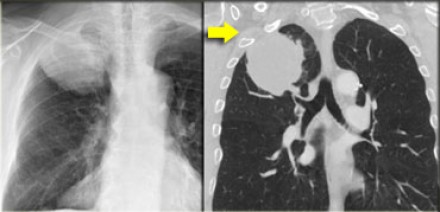

N3 - стадия При N3-стадии визуализируют контралатеральную медиастинальную или контралатеральной хиларную лимфаденопатию или лимфааденопатию надключичных узлов. Считается нерезектабельным состоянием. |

На снимках представлены два пациента с раком легких и лимфаденопатией на

стороне поражения и контралатеральной стороне. |

N3-стадия При N3-стадии визуализируют контралатеральную медиастинальную или контралатеральной хиларную лимфаденопатию или лимфааденопатию надключичных узлов. Считается нерезектабельным состоянием. |